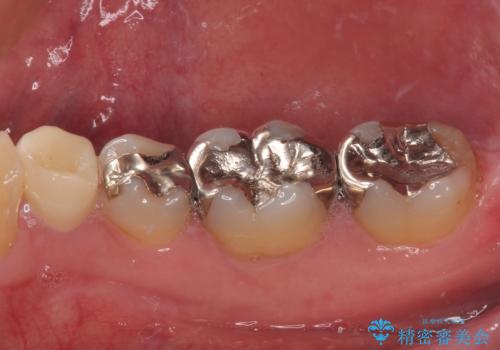

審美面、機能面共に満足していただけました。

順次、後ろにある不適合のメタルインレーの部位をやり替えていく予定です。